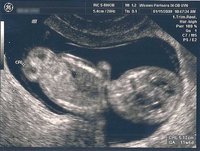

¿Acertó el ginecólogo con el peso al hacer la última ecografía?

PartoUna de las razones de por qué los ginecólogos son ginecólogos y no adivinos es que a la hora de hacer predicciones suelen acertar bastante poco. No es culpa suya, no es fácil saber cuándo va a parir una mujer y por eso siempre digo que...